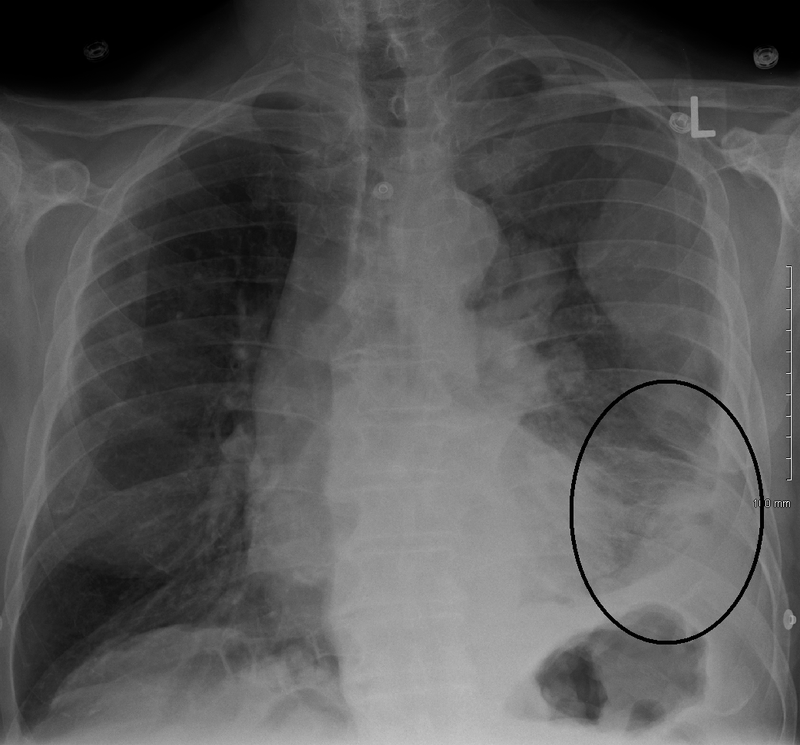

Mesothelioma is a malignant neoplasm of mesothelial cells.

Mesothelioma is strongly linked to occupational exposure to asbestos.

Mesothelioma presents with:

- Chest pain

- Dyspnea

- Recurrent pleural effusions